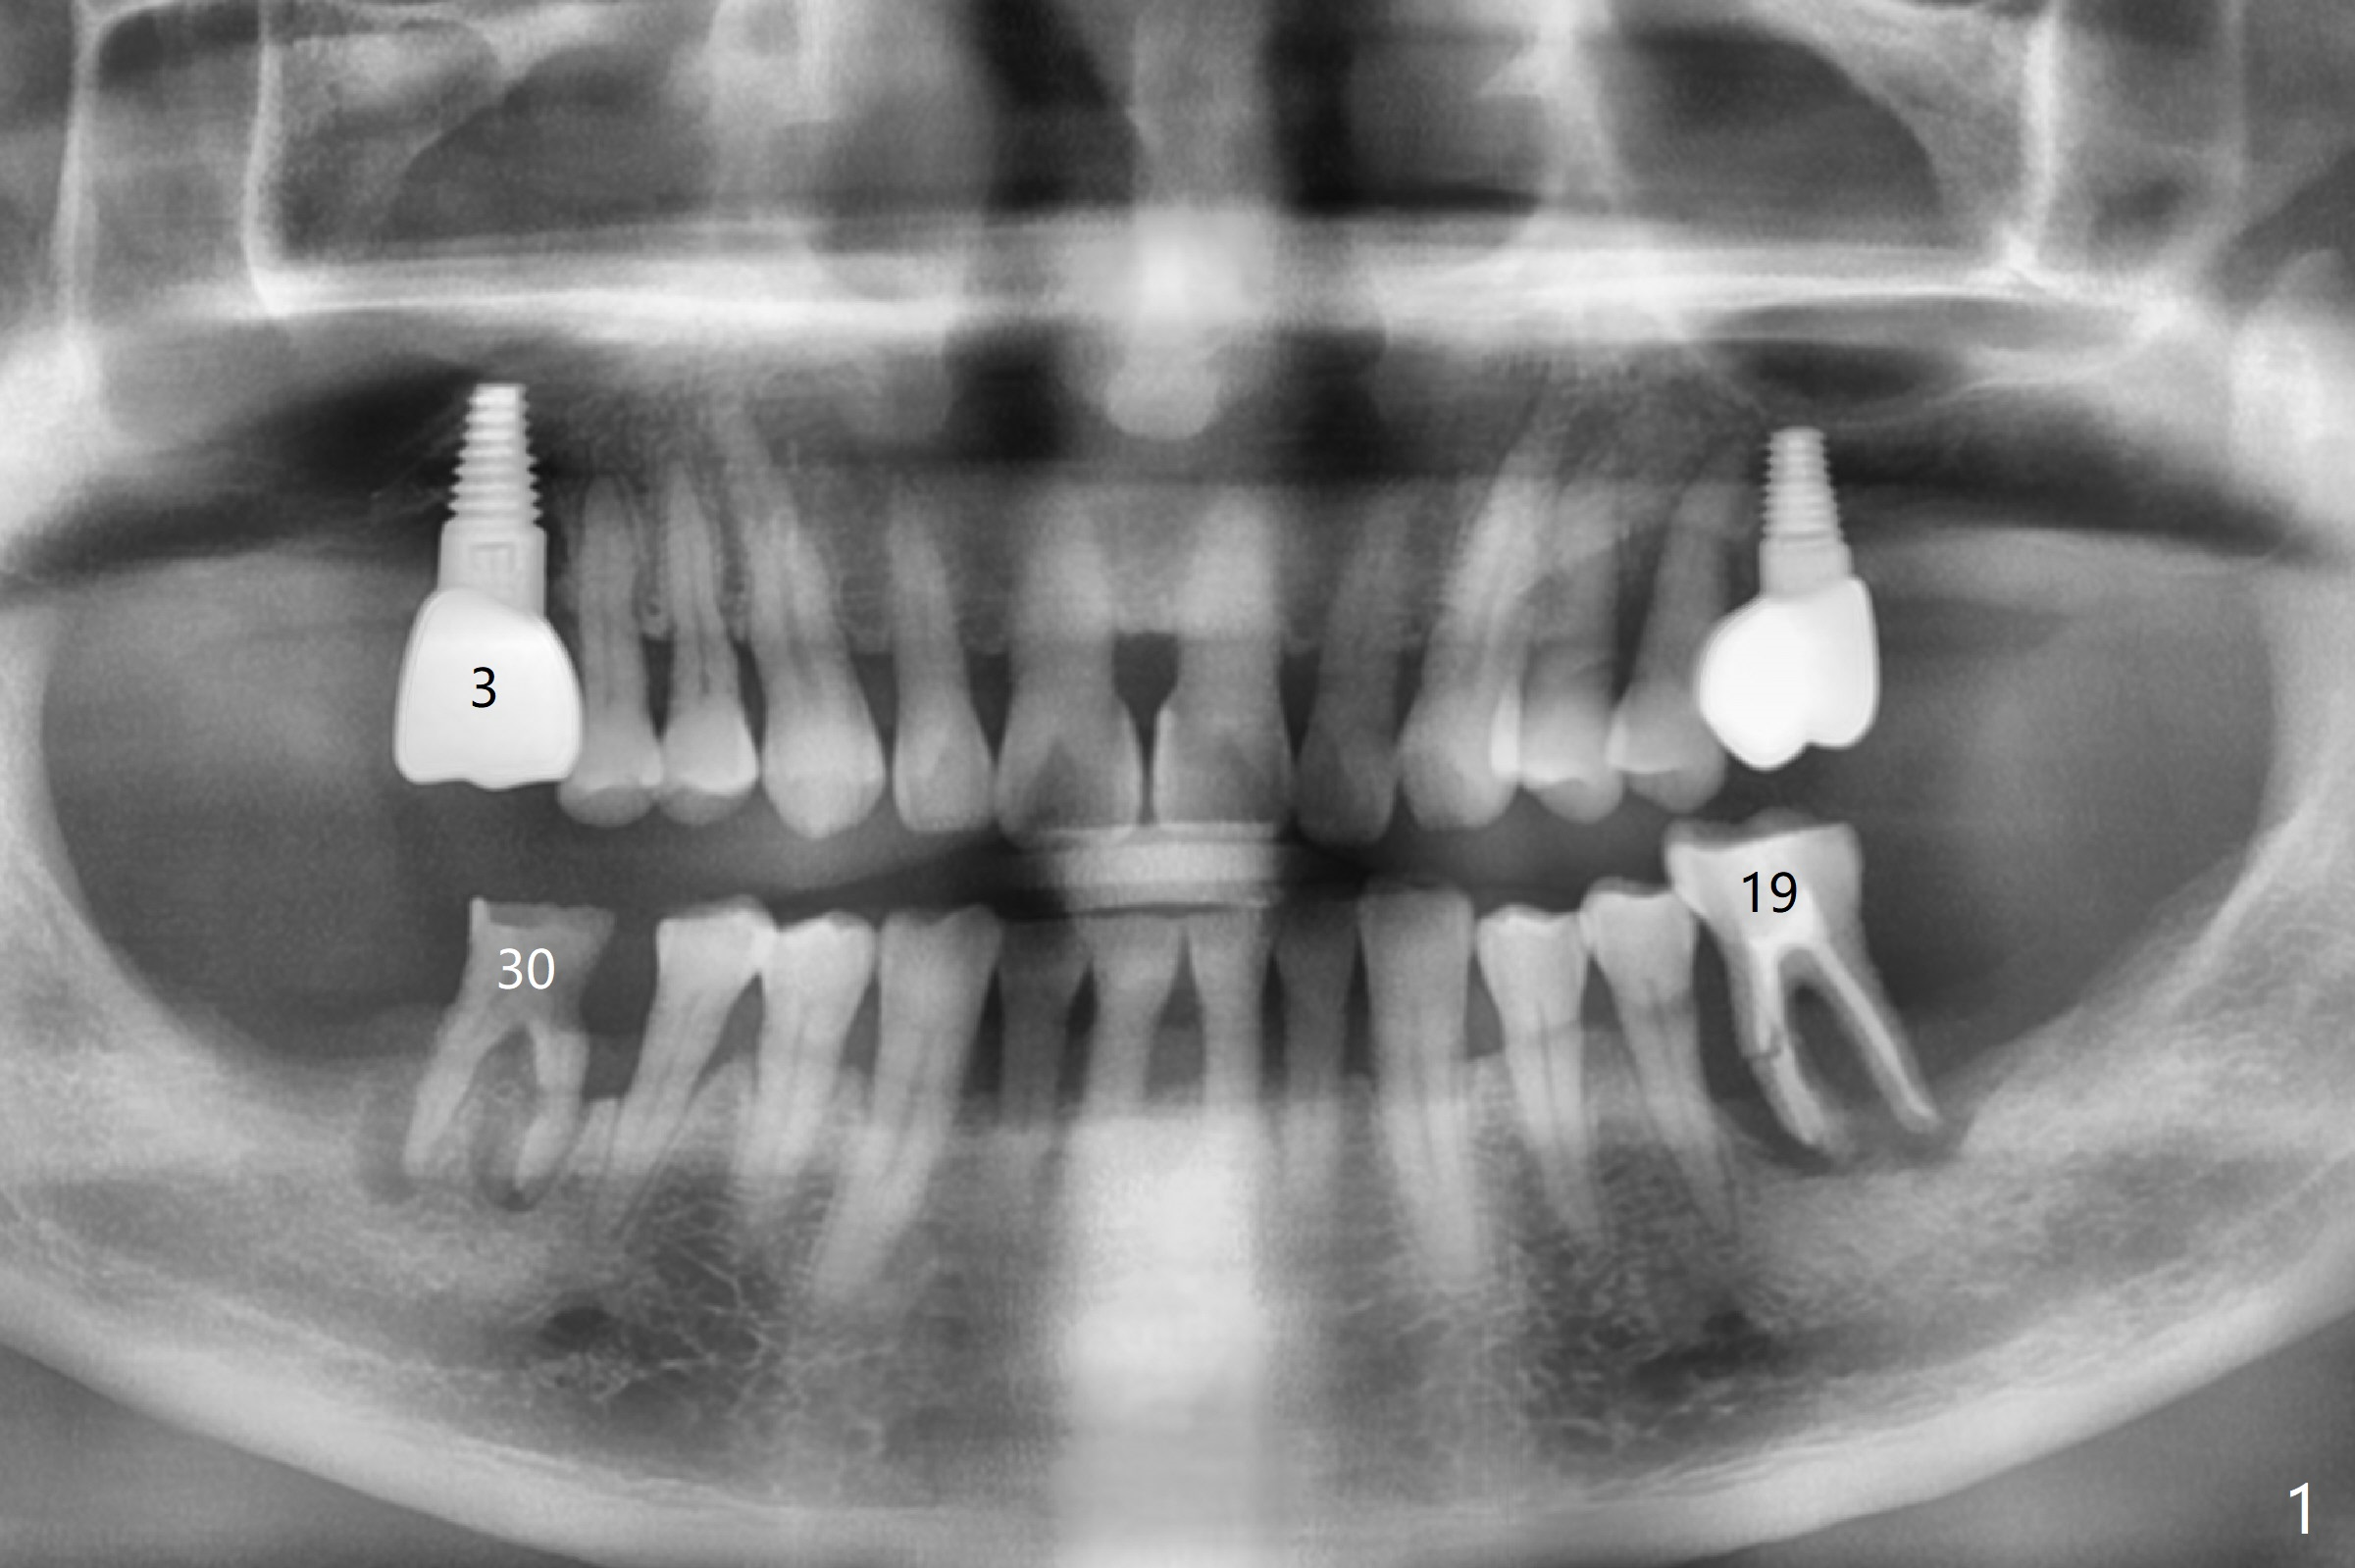

Bone Loss Dictates Position of Implant

Placement M

When the patient finally agrees to have the tooth #19 to be extracted for implant (Fig.1), there is also mesial bone loss associated with mesial root fracture (Fig.2). To avoid truncation of the blood vessels toward the apex of the tooth #20 (Fig.2 black shadow and red line; Fig.4-6 (lab design) red symbols), a 5x10 mm implant will be placed more distal than the earlier design when the septum was present. The implant is also to be placed slightly higher than the native bone to improve crown/implant ratio; i.e., equical to the buccal, lingual and distal crests (Fig.3-6). Allograft will be placed in the gaps. After distal placement with minor axial change, new treatment plan is born. Return to Lower Molar Immediate Implant, Prevent Molar Periimplantitis (Protocols, Table), Trajectory, Weichat Xin Wei, DDS, PhD, MS 1st edition 01/14/2019, last revision 12/28/2019